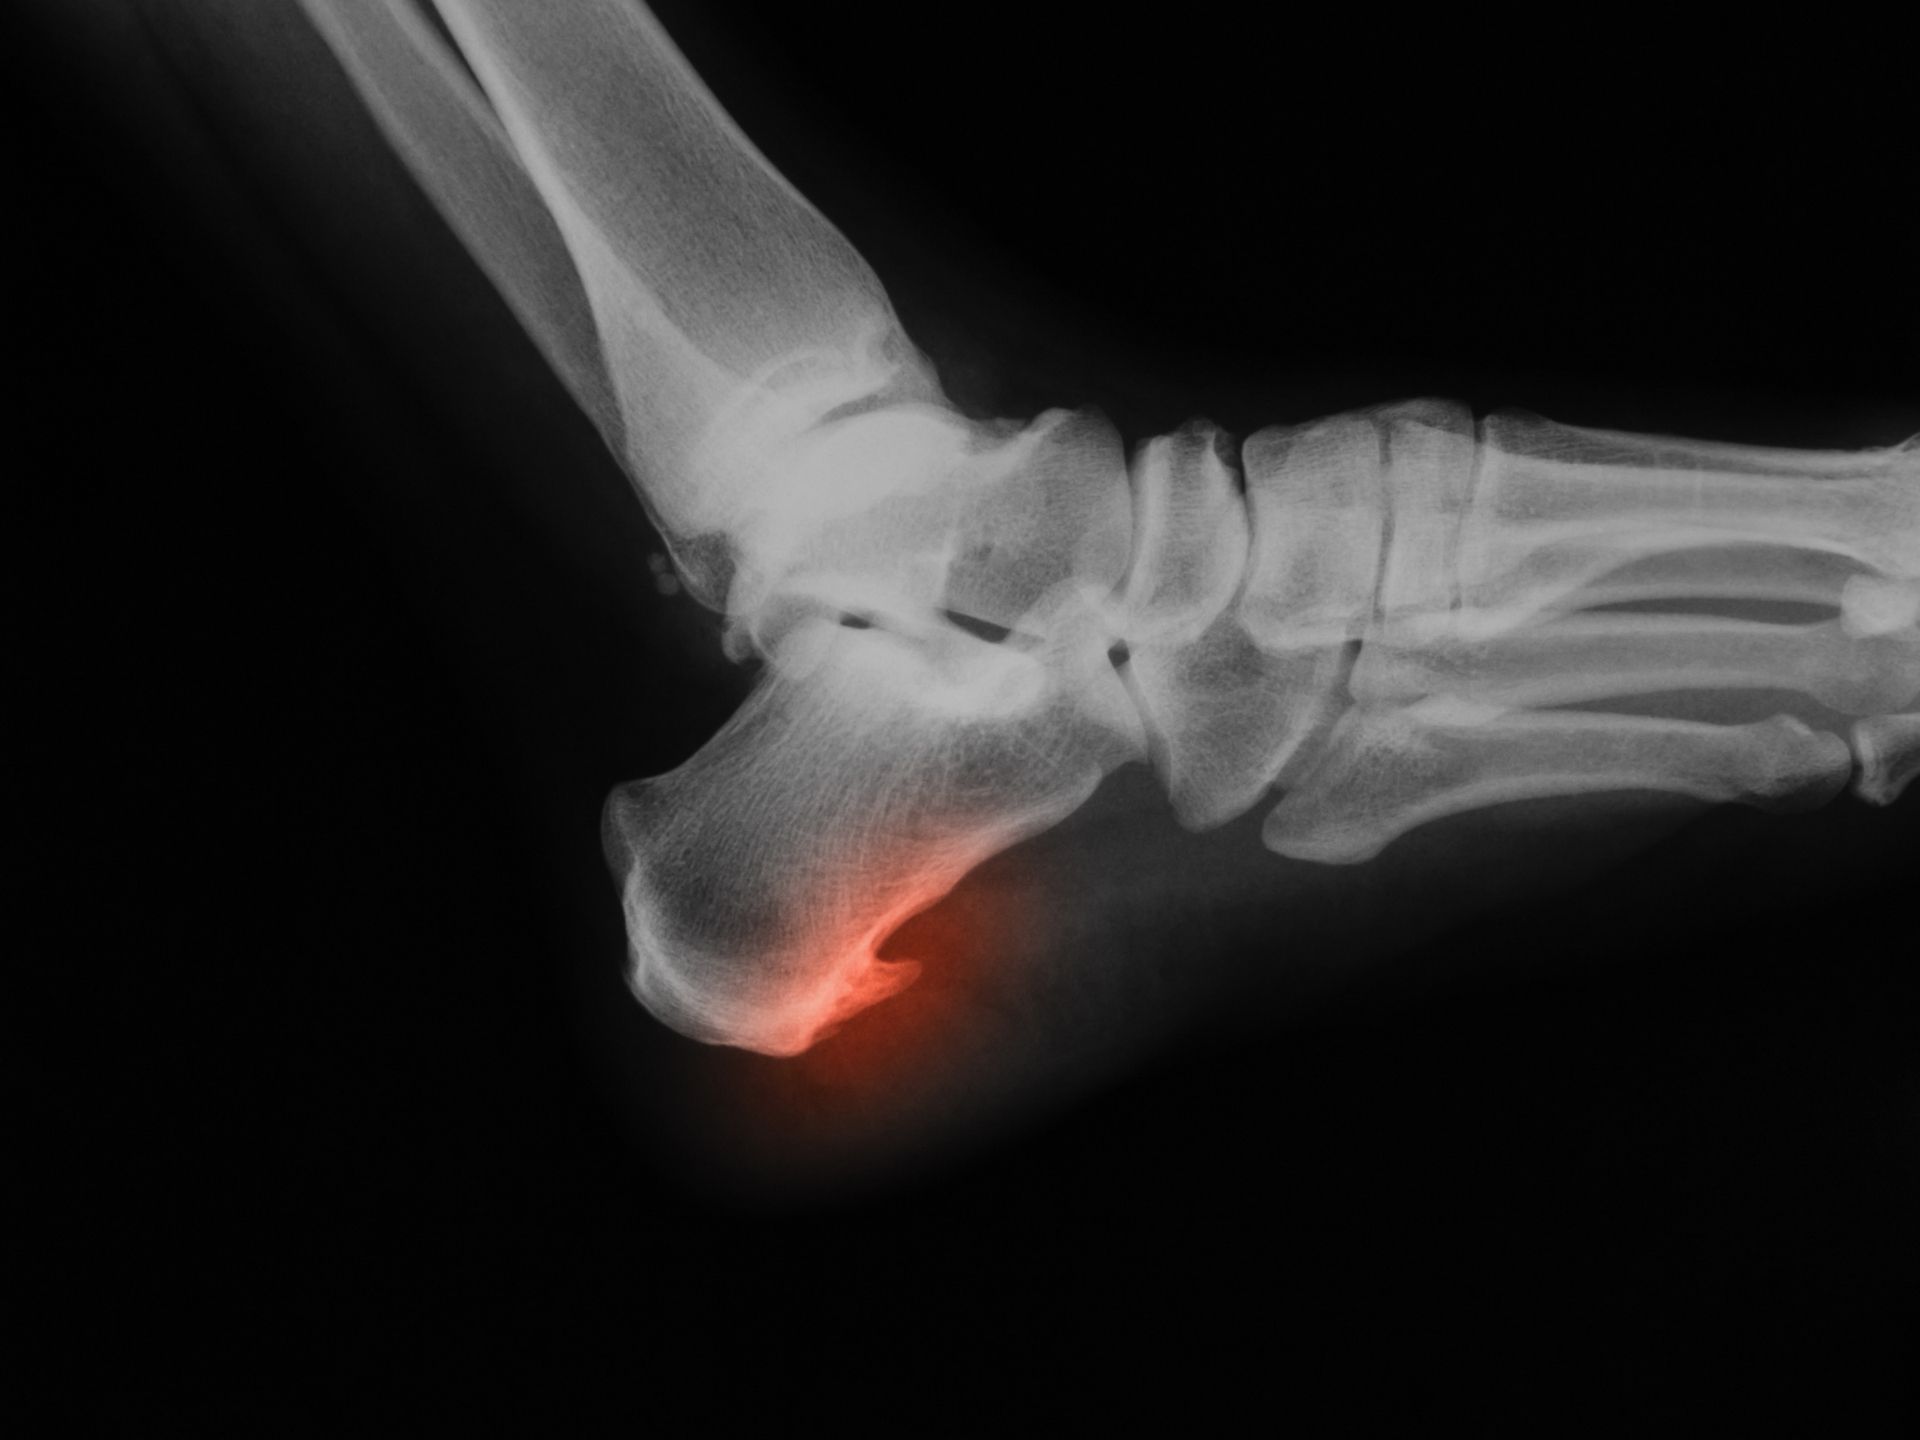

WebRiabilitazione dopo una lesione spinale. Il recupero dopo una lesione del midollo spinale dipende dalla sede (livello) e dall’entità del danno. Quanto più alto è il livello della. WebIn effetti, la radiografia, dopo le terapie per verificare lo stato della spina è davvero inutile. Il paziente continuerà a presentare la spina, ma, se la terapia sarà efficace, senza più. WebChiamata anche spina dorsale, la colonna vertebrale è costituita da 32 vertebre separate da dischi fibro-cartilaginei. È composta da cinque zone:. cervicale; toracica; lombare;. WebLa velocità dipende dalle sensazioni del paziente. Durante la prima fase di guarigione i pazienti con una lesione del tendine del sovraspinato dovrebbero evitare movimenti di. WebLa velocità di recupero dipende dal tipo di intervento chirurgico, dall'impegno del paziente nel lavorare a stretto contatto con il fisioterapista, dal movimento e dall'attività fisica. WebLo sperone calcaneare, se non trattato per tempo, può portare varie complicazioni come la fascite plantare, un’infiammazione della pianta del piede, o.